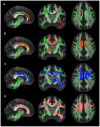

Alzheimeŕs disease (AD) represents the most prevalent neurodegenerative disorder that causes cognitive decline in old age. In its early stages, AD is associated with microstructural abnormalities in white matter (WM). In the current study, multiple indices of diffusion tensor imaging (DTI) and brain volumetric measurements were employed to comprehensively investigate the landscape of AD pathology. The sample comprised 58 individuals including cognitively normal subjects (controls), amnestic mild cognitive impairment (MCI) and AD patients. Relative to controls, both MCI and AD subjects showed widespread changes of anisotropic fraction (FA) in the corpus callosum, cingulate and uncinate fasciculus. Mean diffusivity and radial changes were also observed in AD patients in comparison with controls. After controlling for the gray matter atrophy the number of regions of significantly lower FA in AD patients relative to controls was decreased; nonetheless, unique areas of microstructural damage remained, e.g., the corpus callosum and uncinate fasciculus. Despite sample size limitations, the current results suggest that a combination of secondary and primary degeneration occurrs in MCI and AD, although the secondary degeneration appears to have a more critical role during the stages of disease involving dementia.